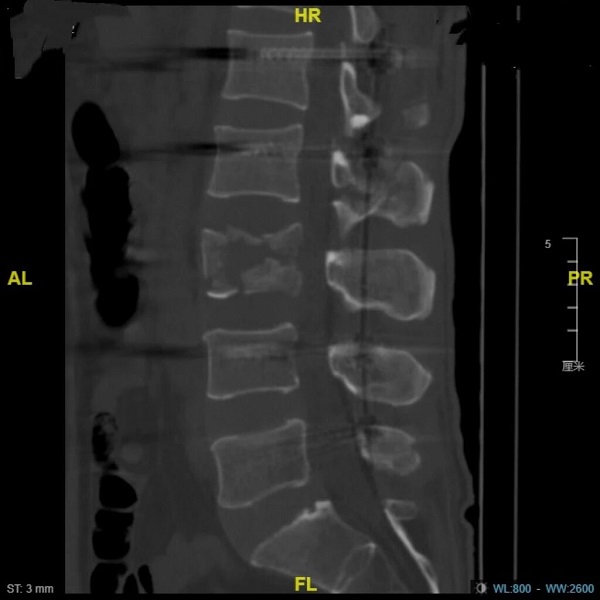

术后图片:椎体高度基本恢复

整场手术持续190分钟,出血仅110毫升。术后第二天,李先生右腿的力量当即有好转。一周后复查,椎管侵占解除,面积恢复96%。更令人欣喜的是,术后一个月,李先生的双下肢肌力奇迹般地恢复至正常(5级),二便功能也重获控制。